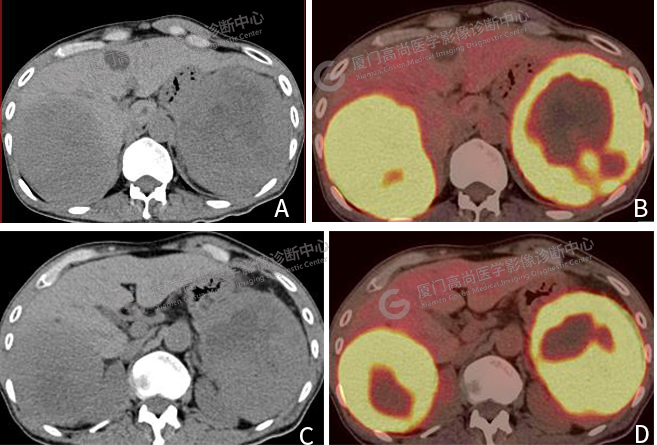

圖片圖3:A、 C CT圖像,肝臟右葉巨大腫塊影,脾臟內(nèi)巨大軟組織腫塊,代謝顯著增高。B、 D PET/CT融合圖像,腫塊代謝異常增高。

肝臟右葉見(jiàn)一巨大腫塊影,大小約10.0×8.6cm,F(xiàn)DG攝取明顯增高,SUVmax 16.1。脾臟內(nèi)見(jiàn)一巨大軟組織腫塊,大小約11.6×10.2cm,F(xiàn)DG攝取明顯增高,SUVmax 18.3(圖3)。